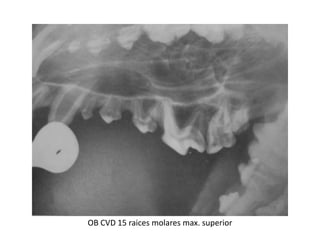

OB CVD 15 raices molares max. superior